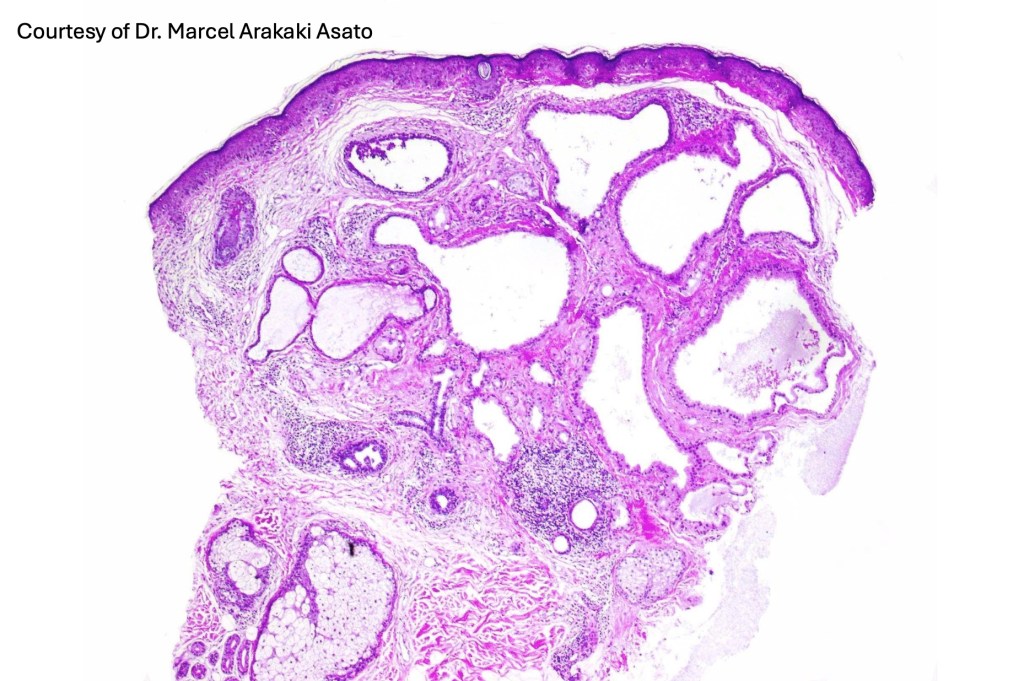

Histological features

•Pseudo-encapsulated unilocular or multilocular

•Adenomatous/papillary component (cystadenoma)